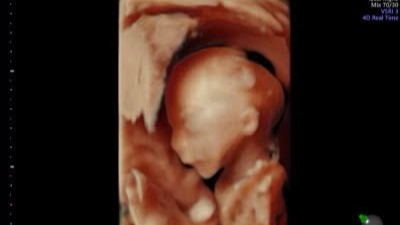

The baby boy (Adrain) has several medical issues, including DS and IUGR. He is very very tiny, <1% of where he should be. There is a very strong possibility that he will not survive to the age of viability, which in his case would be closer to 28 weeks as opposed to 26. Due to these factors, they caution that he might not make it, and might be stillborn, but we know that anything can happen if it's God's will. As of now, even though his dopplers show his cord blood flow is at times reversed, and even periodically absent, he continues to show slight gains... so we pray for his highest and best outcome.. trusting and having faith.

Because this is a twin pregnancy, this puts healthy baby girl (Aliana) at increased risk of everything from premature delivery to also being stillborn. As of now though, she is happy, healthy, growing normally and showing no signs of distress.